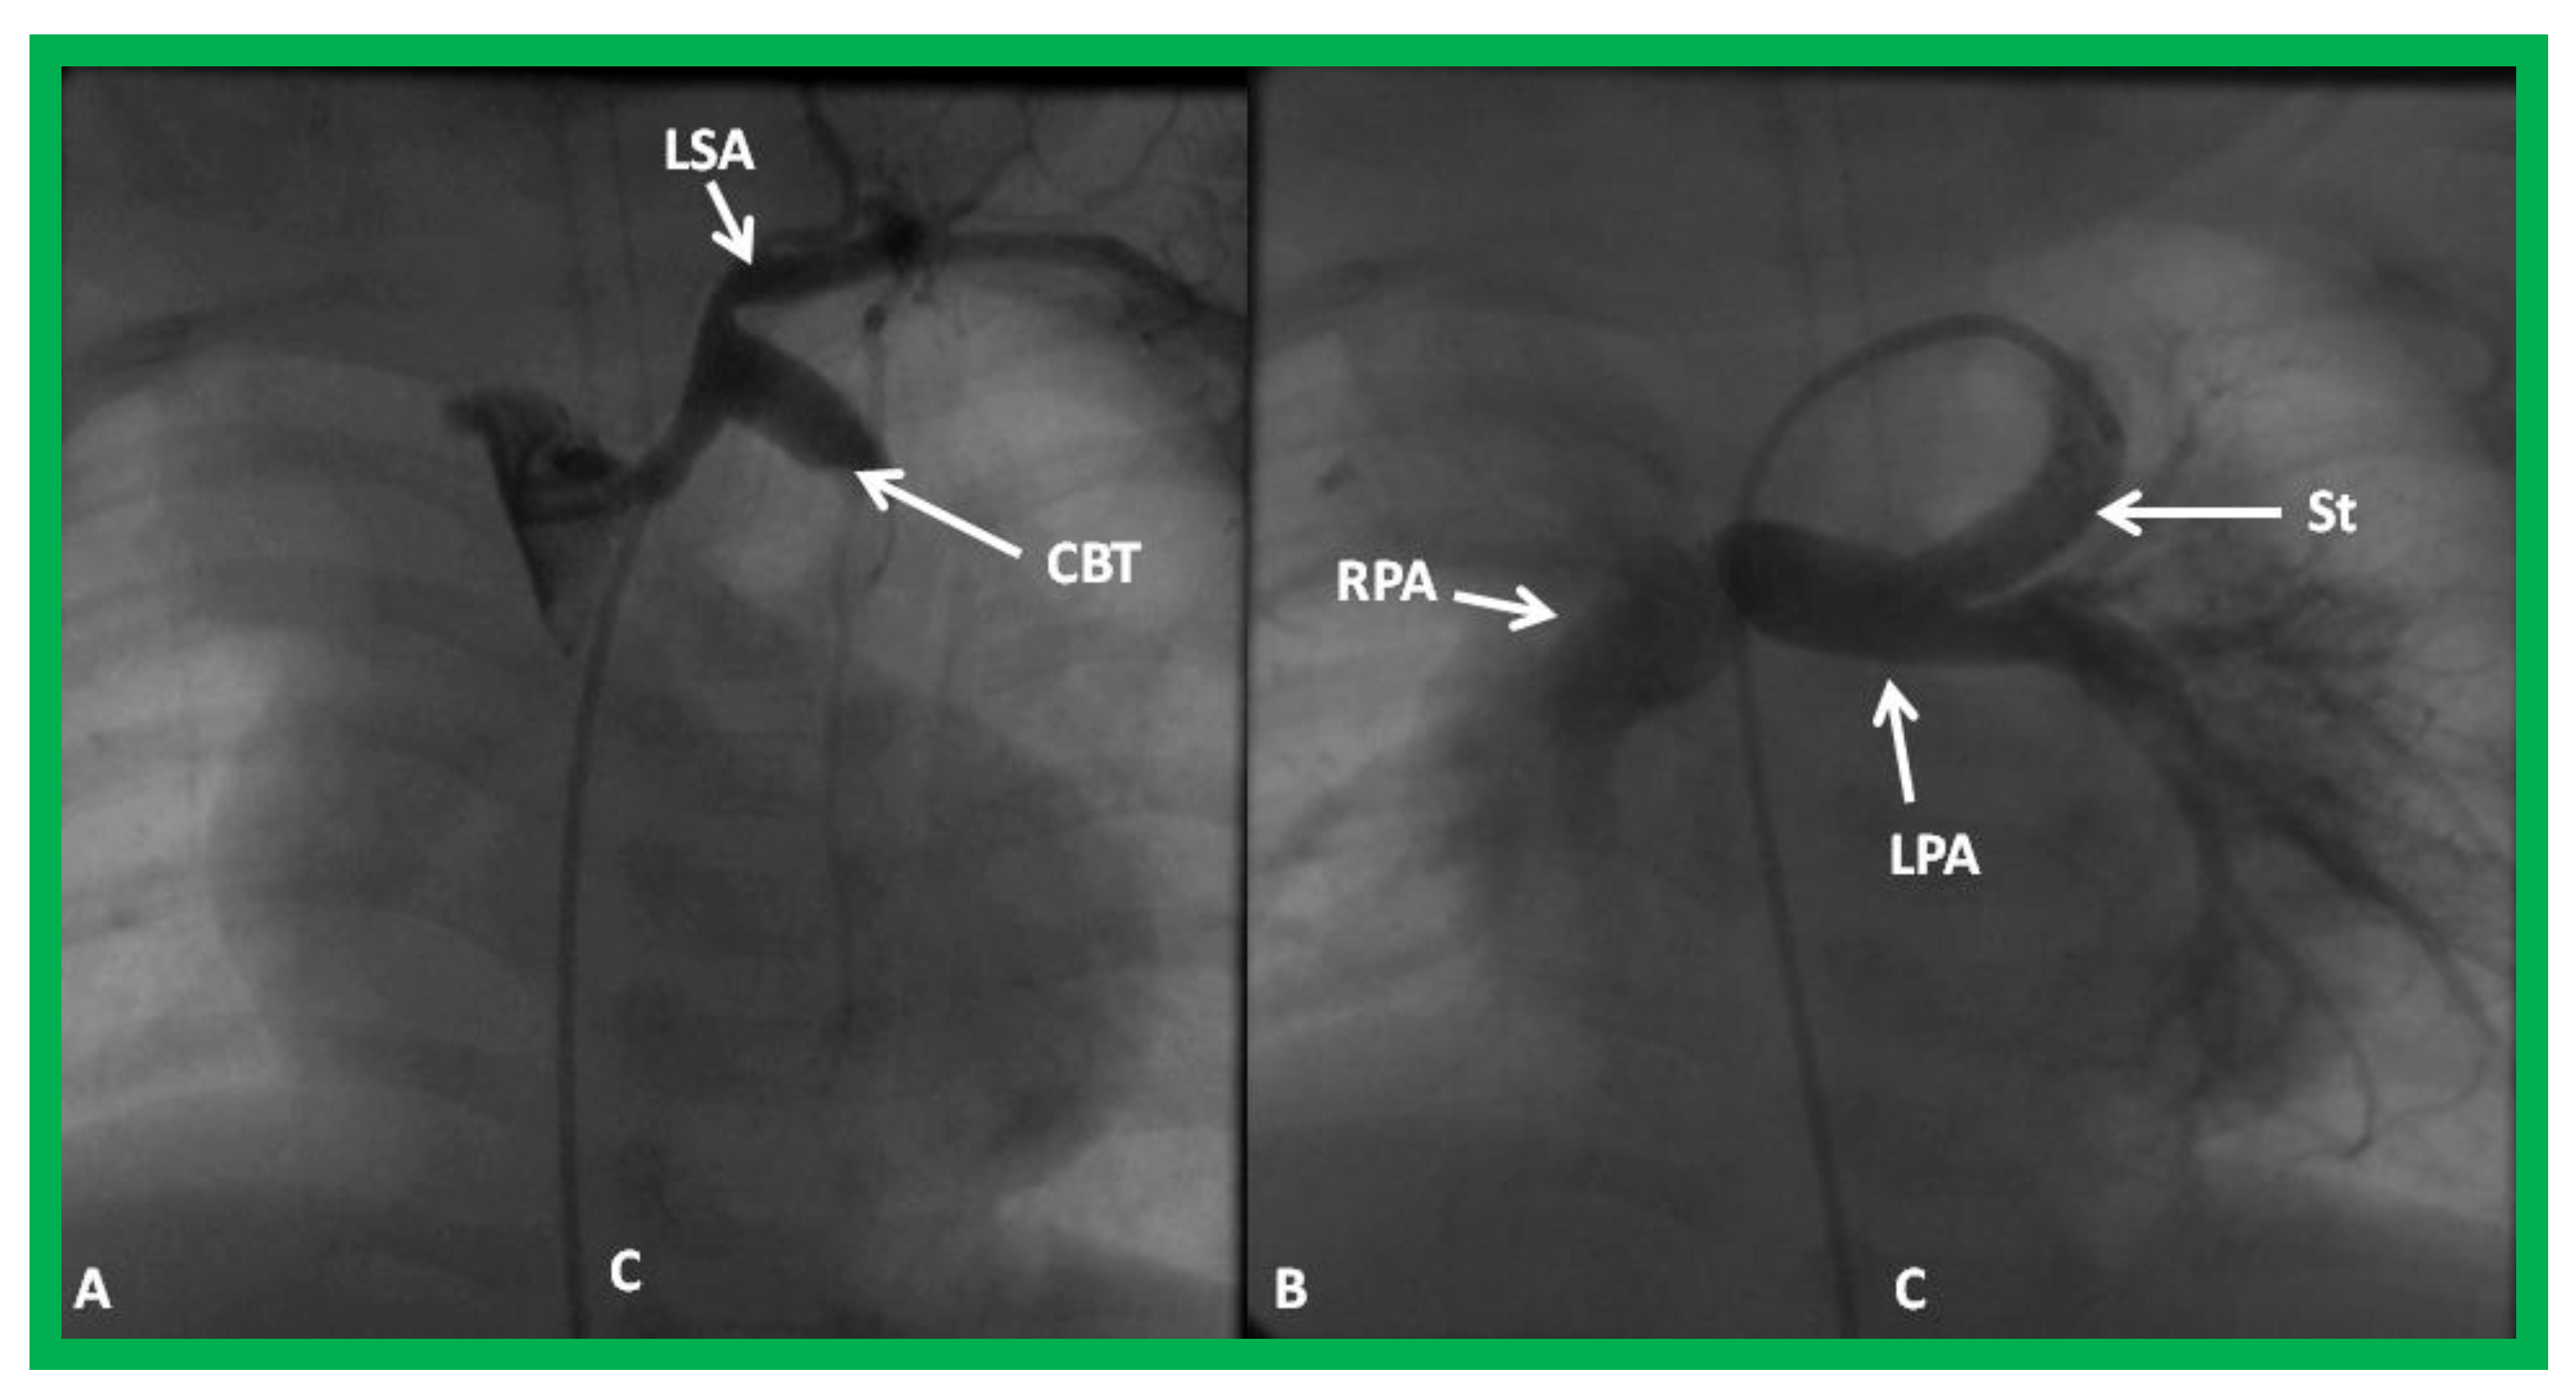

Figure 27.

Selected cineangiographic frame demonstrating clotted Blalock-Taussig (CBT) shunt (A). After unsuccessful recanalization with mechanical thrombolysis and balloon angioplasty, a stent (St) was implanted (B). Angiography with tip of the catheter (C) in the proximal portion of the stent showed complete opening of the BT shunt with visualization of right (RPA) and left (LPA) pulmonary arteries. LSA, left subclavian artery. Reproduced from Reference [61].